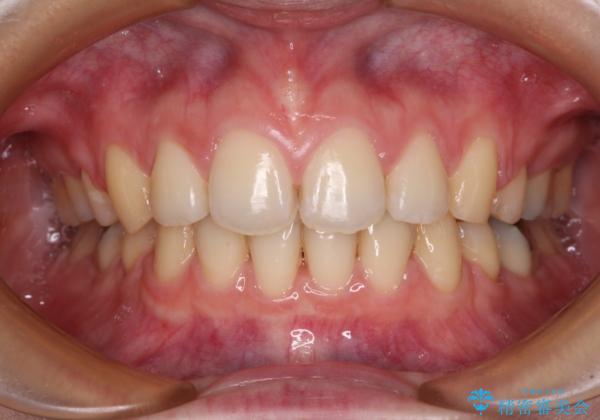

- 口元の突出感と口の閉じにくさを気にして来院された患者様です。

上下左右第一小臼歯4本を抜歯し、ワイヤー装置にて口元を引っ込めるよう矯正治療を行うこととしました。

ご友人などがびっくりするほど口元の突出感を改善することができ、患者様には大変満足していただきました。